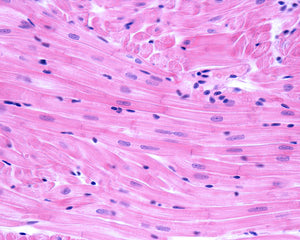

Research using the DOCA-salt rat model of hypertension observed that treatment with Avemar (FWGE) improved cardiac function, decreased macrophage infiltration resulting in decreased collagen deposition in the ventricular myocardium, reversed an increased stiffness of the left ventricle in the diseased hearts and attenuated oxidative stress measured as plasma malondialdehyde concentrations without changing systolic blood pressure.